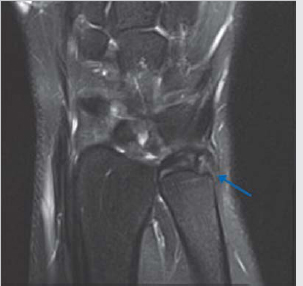

Triangular fibrocartilage complex tear

Cause of ulnar sided pain.

Triangular fibrocartilage disc is T2 hypointense (black).

Two distal attachments to ulna—fovial and styloid; can have some T2 grayish signal normally due to fibrovascularity.

T2 hyperintense fluid signal to diagnose tear (► Fig. 4.4).